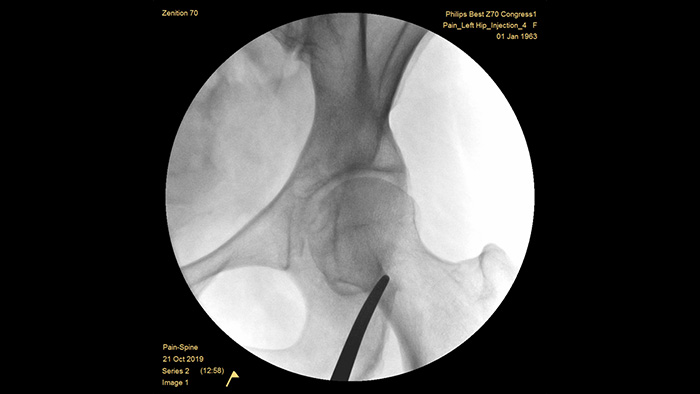

Unsere Flachbilddetektorsysteme der vierten Generation bieten hervorragende Bildschärfe bei komplexen Strukturen mit hoher Gewebedichte. Das kompakte Design des Systems lässt ausreichend Raum und ermöglicht die einfache Positionierung bei der Behandlung chronischer Gelenkschmerzen. Unser Position Memory2 sorgt für eine auf Anhieb richtige Positionierung und damit auch für einen geringeren Bedarf an Scout Images (Orientierungsaufnahmen)3 sowie effizientere schmerztherapeutische Arbeitsabläufe. Zenition 70 ist mit drei Detektorgrößen verfügbar: der Flachdetektor mit 26 x 26 cm deckt große anatomische Bereiche ab, während der Flachdetektor mit 21 x 21 cm um den Patienten herum viel Platz zum Arbeiten lässt.

Die speziell vorkonfigurierte Untersuchungseinstellung für die Schmerztherapie ermöglicht die einfache Einrichtung des Systems während den interventionellen Schmerztherapieverfahren.

Die richtige Tiefe des vollständig gewichtsausgeglichenen C-Bogens ermöglicht bei der Bildgebung der Lendenwirbelsäule und Hüfte selbst bei adipösen Patienten einen mühelosen Zugang. Sie unterstützt auch die Positionierung über dem Tisch, selbst bei Tischen mit großer Basis.